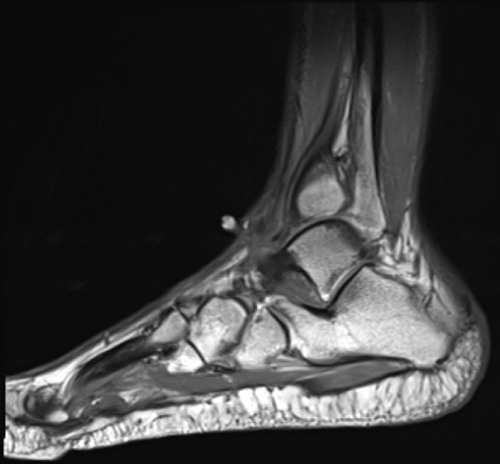

Figure 3: Sagittal T1-weighted MRI showing increased signal intensity at the subcutaneous tissue at the anterior aspect of the ankle. A fibroma localizing from the ankle joint capsule has been described by Ciatti, et al. [16]. View Figure 3

Figure 4: Sagittal T2-weighted MRI showing decreased signal intensity at the subcutaneous tissue at the anterior aspect of the ankle. Tenosynovitis would likely show increased uptake on this imaging modality [17]. View Figure 4